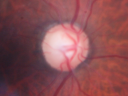

67-year-old man has proliferative diabetic retinopathy in both eyes with vitreous hemorrhage in the left eye. He has had pan retinal laser in the left eye. The vitreous hemorrhage has been there for greater than two years and his vision is still hazy. He takes Lumigan in both eyes for his glaucoma.

VISUAL ACUITY: OD 20/40, OS 20/40. IOP: OD 12, OS 11. The right eye has a posterior chamber intraocular lens in good position, as does the left eye.

OD: Vertical C/D ratio is 0.8. There is neovascularization on the inferior and superior pole of the optic nerve.

The macula is dry. There are ischemic changes in the periphery including ghost vessels.

OCT SCAN: The OCT scan of the right eye shows the macula to be flat. The left eye shows a stable macular pucker. Photos confirm clinical findings.

FLUORESCEIN ANGIOGRAPHY: Fluorescein angiography shows leakage from the neovascularization on the nerve in the right eye and in the inferotemporal of the macula in the left eye and also the peripherals sweeps in the right eye show significant non perfusion, especially inferonasally.

1. PROLIFERATIVE DIABETIC RETINOPATHY – BOTH EYES

2. NON CLEARING MILD VITREOUS HEMORRHAGE – LEFT EYE

3. GLAUCOMA

DISCUSSION: I explained to the patient with the proliferative retinopathy in the right eye, he has a high risk of vision loss, especially given that he has blood already in his left eye. I would like to protect the right eye from a similar fate. I started pan retinal laser in the right eye today